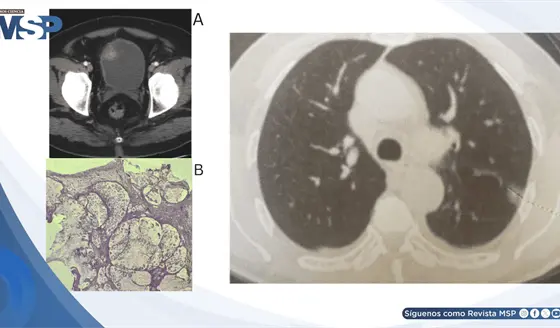

Hematuria reveló adenocarcinoma mucinoso de células en anillo de vejiga con metástasis pulmonar y ósea